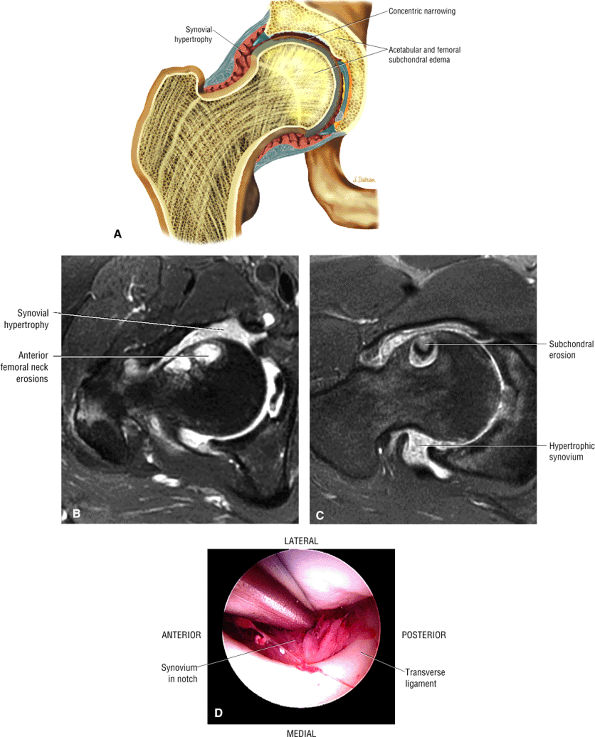

The stellate lesion or crease represents a normal bare area superior to the acetabular fossa.

An enlarged or hypertrophied labrum may occur in patients with mild DDH.17 We have observed a femoral head chondral crease (Fig. 3.66) in these patients, creating a demarcation trough medial to a femoral head bump immediately proximal to the physeal scar. Patients who demonstrate femoroacetabular impingement (or lateral acetabular rim syndrome in DDH) also have direct impingement between the lateral acetabular labrum and the femoral head.

FIGURE 3.51 ● (A) The stellate crease (arrows) is shown above the acetabular fossa (F) and within the lunate surface of the acetabulum. The stellate crease, (lesion) represents a bare area deficient in hyaline cartilage and not degeneration. Arthroscopically, this bare area may appear as an indentation. The femoral head (H) is indicated. Anterior is down and posterior is up. (B) The articular lunate surface of the acetabulum. The osseous acetabular rim is angled anteroinferior relative to the sagittal plane. The adult aperture angle is 17°.